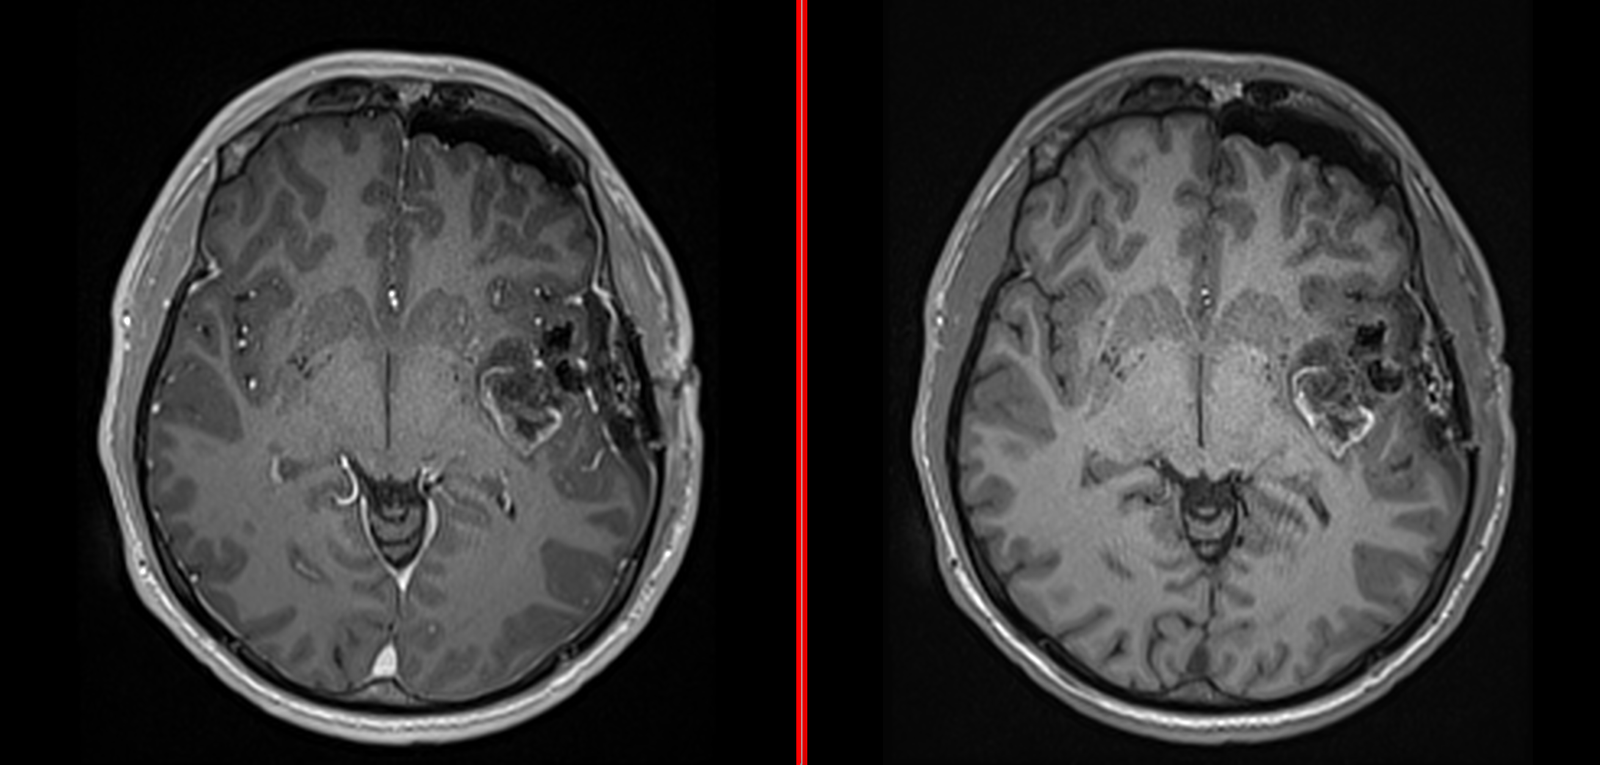

Ai primit un diagnostic de tumoră cerebrală? Aici găsești sprijinul, informațiile și direcțiile de care ai nevoie pentru a merge mai departe.

Chiar și pentru cele mai agresive tumori, există tratamente care pot salva vieți sau pot câștiga timp valoros. În peste 20 de ani de practică medicală, am întâlnit foarte puține tumori cu adevărat „inoperabile”.

Tumorile glioneuronale sunt neoplasme rare ale sistemului nervos central (SNC), care combină elemente neuronale și gliale în proporții variabile. Aceste...